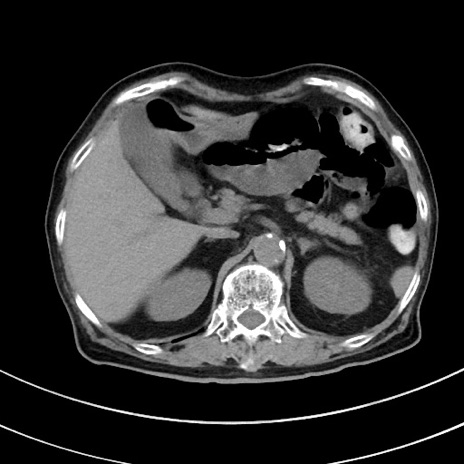

症例33(横断像)

【症例】70歳代 女性

【主訴】心窩部痛

【現病歴】延髄病変の精査・加療にて神経内科入院中。本日より心窩部痛あり。

【既往歴】虫垂炎

【身体所見】右下腹部を中心に圧痛と反跳痛あり。

【データ】WBC 10900、CRP 0.02